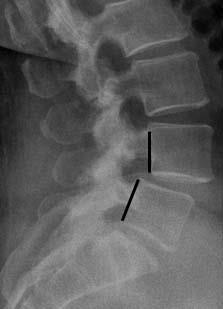

Thoracic disc herniation | Radiology Case | Radiopaedia.org from images.radiopaedia.org For instance a herniated disc can cause nerve compression at the level of the disc, but also at here a 25 year old patient who presented with low back pain. For example, if a spinal disc herniation in the low back is impinging on the nerve that goes to the leg and causing symptoms of foot drop, then the herniated disc should be treated. Depending on the level of disc injury, you may require surgery or just undergo back pain treatment. Most cases of herniated disc are in the lower back. This is called a myelogram. This test can show pressure on your spinal cord or nerves due to multiple herniated disks or other conditions. It is sometimes called a bulging, protruding, or some of these people will have low back pain and leg pain caused by a herniated disk. This may place pressure on nearby nerves or the the lower back (lumbar area) of the spine is the most common area affected by a slipped disk.

For instance a herniated disc can cause nerve compression at the level of the disc, but also at here a 25 year old patient who presented with low back pain. What is a herniated lumbar disc? A herniated (slipped) disk occurs when all or part of a disk is forced through a weakened part of the disk. However they can also occur in the cervical and thoracic spine. This test can show pressure on your spinal cord or nerves due to multiple herniated disks or other conditions. Herniated disks occur most often in the lower back. Video features three extension stretching movements: In many cases, they cause no symptoms and require no treatment. Disc herniation most commonly occurs in the lower back (lumbar spine) and involves the displacement of disc material beyond the what does a herniated disc feel like? This is called a myelogram. In this article, learn what causes disks to slip, how to prevent this, and what complications. Lumbar spine mri, lower back x ray, herniated disc mri, disc protrusion. If you find that most of your discomfort is in your lower back, butt, and legs you most likely have a herniated disc l5 l4.

Disc herniation caused by a viscoelastic nucleus after total lumbar disc replacement—a case ... from cdn.amegroups.cn In many cases, they cause no symptoms and require no treatment. Lumbar herniated disc treatment may include extension exercises to help you ease pain while strengthening low back muscles. Application of radiation to produce a film or picture of a part of the body can show the structure of the vertebrae and the outline. A ruptured disc causes shooting pain in the cervical (neck), thoracic, or lumbar (back) region of the spine. Lower spine herniated disc topics. A herniated disk is a condition that can occur anywhere along the spine, but most often occurs in the lower back. Lower back pain is typically the first symptom of a lumbar disc herniation. For instance a herniated disc can cause nerve compression at the level of the disc, but also at here a 25 year old patient who presented with low back pain.